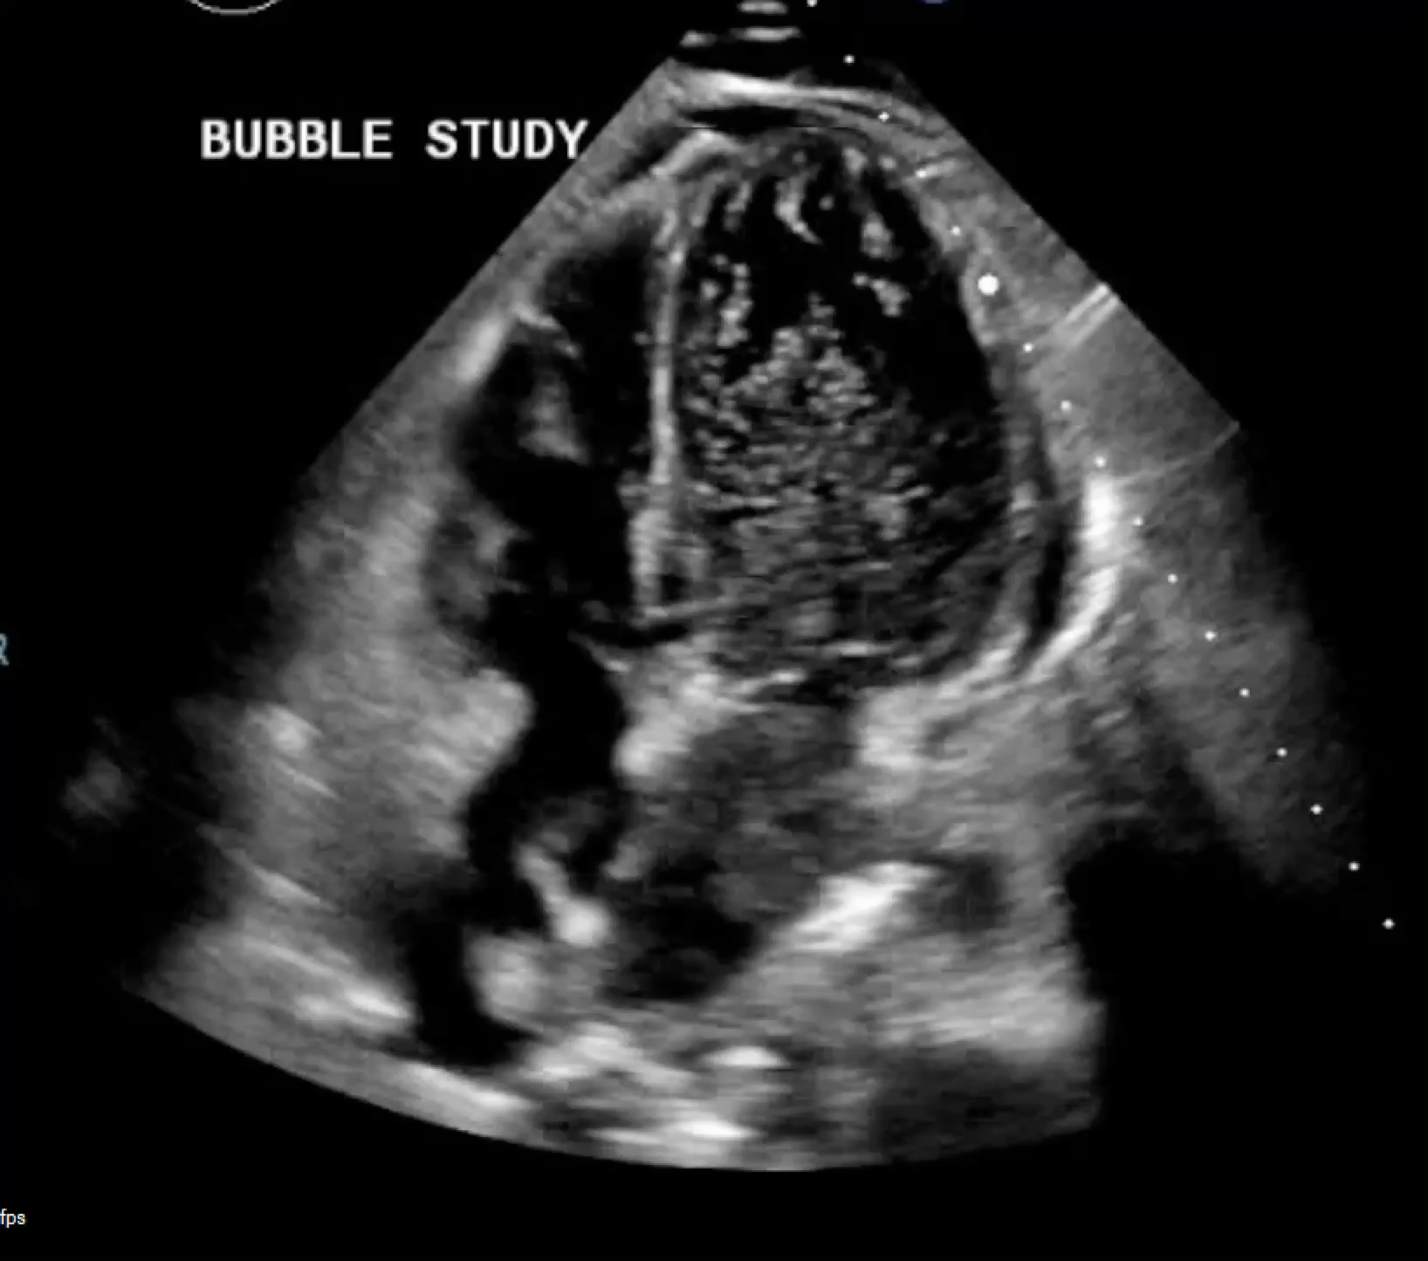

A 33-year-old man with ESRD on hemodialysis was admitted with subacute cough and weight loss, diagnosed with necrotizing MSSA pneumonia. His hospitalization was complicated by respiratory failure, septic shock, and transient effusive-constrictive pericarditis. TTE revealed an EF of 50–55%, normal RV function, small pericardial effusion, mild aneurysmal interatrial septum, and an unexpected bubble study finding: agitated saline injected via a left-arm IV resulted in bubbles first appearing in the left atrium via pulmonary veins (Figure 1), with robust left-sided opacification and delayed right-sided filling. No interatrial transit of bubbles was observed.